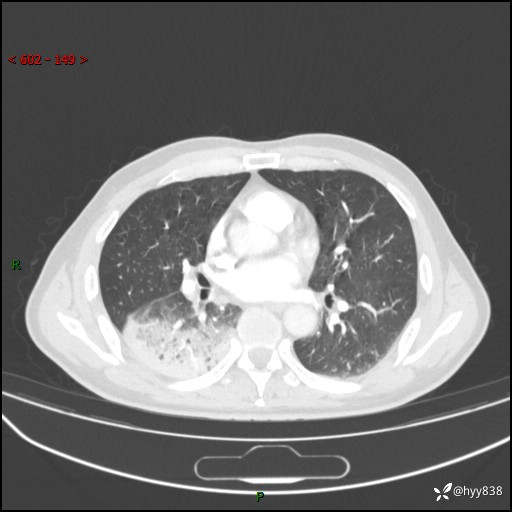

63岁/男,发热5余天。精彩好病例,“大叶性肺炎”,等你来诊---结果公布~

【患者信息】:63岁/男

【主诉】:发热5余天

【现病史及既往史】:患者5余天无明显诱因出现畏寒寒战发热,最高体温39.5℃,发热无明显昼夜规律,伴全身乏力、头晕,无头痛、无咳嗽咳痰、无胸痛咯血、无气短、无腹痛腹泻、无尿频尿急尿痛等不适,于当地市第五人民医院就诊,予以抗感染等治疗(具体不详)后发热无明显好转,1天前查胸部CT提示右下肺感染,为求进一步诊治,门诊以“社区获得性肺炎”收治入院; 起病以来,患者精神、食欲一般,睡眠可,大小便正常,体力体重较前无明显变化。

【检查】:胸部CT增强